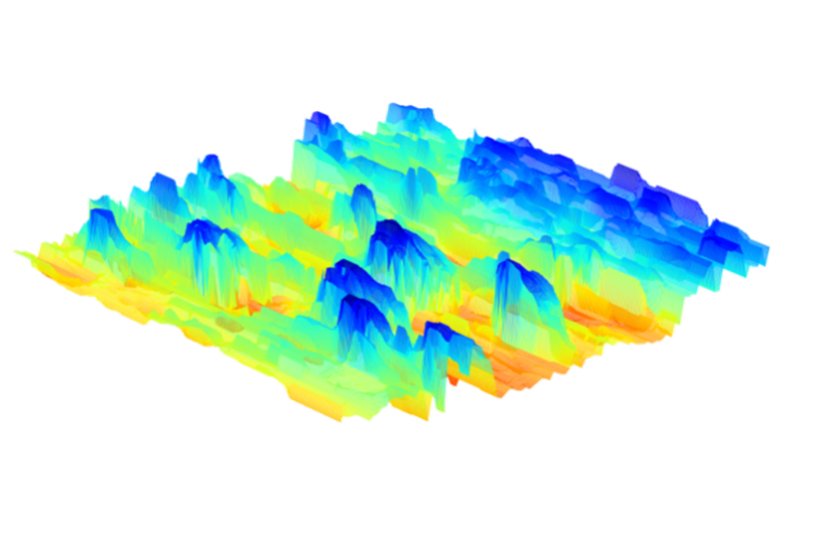

LC-OCT™ imaging of a fingerprint